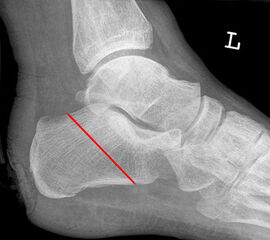

Der kraniale Calcaneus wird so mit der oszillierenden Säge reseziert, dass bei der Fusion mit der Tibia die physiologische Inklination von 30° wieder hergestellt wird (Abb. 48). Wird der Calcaneus zu steil eingestellt, kann das zu erhöhter Druckbelastung am Tuber calcanei und damit zur Ulzeration führen. Eine flache Einstellung des Talus wird von manchen Operateu­ren bevorzugt. Dies ist technisch vielleicht etwas einfacher, führt jedoch zu einer stärkeren Verkürzung. Varus- und Valgusfehlstellungen müssen vermieden werden.